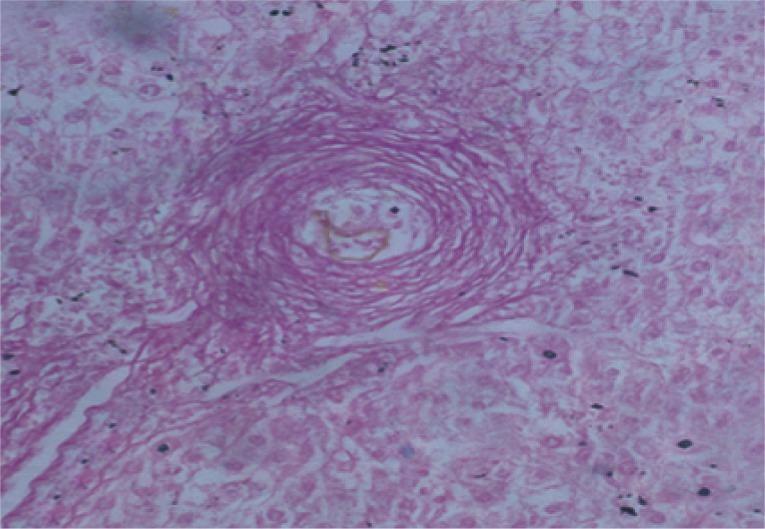

Sirius red staining for collagen

The collagen content of the liver sections stained with Picrosirius red was evaluated quantitatively for the percentage areas of collagen using Computerized Cell Image Analysis. Collagen fibers within the squares of the ocular reticule were counted at ×200 magnification [24].

The mean granuloma count in the treated groups with BMSCs and BMSCs-HGF revealed a marked reduction accompanied by an obvious reduction in the mean granuloma number and diameter (Table 1; Figs. 2, 3).

Collagen content as determined by morphometric image analysis

Morphometric studies using Sirius red staining showed significant decreases in the fibrous tissue in BMSCs and BMSCs-HGF-treated groups compared to the infected control group (Figs. 6,7,8,9,10,11,12,13,14,15).

After treatment with BMSCs alone or in combination with HGF, there was an improvement in the histopathological picture of the liver which included diminution in the number and diameter of granulomas and reduction in the fibrotic content. Similar to the present findings, Abdel Aziz et al. [13] focused on the antifibrotic effect of mesenchymal stem cells (MSCs) on the liver of S. mansoni-infected mice. In their model, once granulomas were formed around the S. mansoni ova, the rate of spontaneous change of the collagen content of the granuloma was low, thereby providing a relatively stable in vivo model for analyzing collagen turnover. The histopathological examination of the liver of the S. mansoni-infected mice showed characteristic granulomas, which were cellular and contained thick collagen bands. After MSCs infusion, the granulomas decreased in size and number and became less cellular, although the concentric fibrous bands were still discernible.

In our study, the extent of fibrosis was estimated by the quantitative morphometric analysis of the collagen content in Sirius red stained liver sections. The results revealed significant decreases in the collagen content after treatment with BMSCs alone or in combination with HGF. In this regard, Ghanem et al. [8] demonstrated that fibrosis developed during the chronic phase of granulomatous inflammation in murine schistosomiasis and it represented a protective function during infection by neutralization and sequencing egg antigens that can potentially damage host tissues. The inhibitory effect of inoculated BMSCs on the collagen deposition may be related to an enhancement of fibrotic degradation rather than a decrease in fibrosis synthesis.